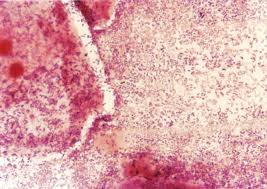

La prueba de papanicolau se diagnostica interpretando el significado de las formas celulares (tamaño de la célula y el núcleo y relación entre ambos) a traves de la visualizacion con el microscopio de las celulas teñidas previamente con colorantes especiales, la laminilla (portaobjetos) ya procesada ,(teñida por el metodo de papanicolau modificado) se recorre en zigzag sin dejar ni una sola area de ver observando todos los elementos que encontramos (bacterias, células de respuesta inflamatoria, maduración celular, flora bacteriana, tipos de células que se encuentren y aspecto de las mismas) este trabajo lo realizamos principalmente los citotecnologos quienes despues de observar las caracteristicas de las celulas de una laminilla determinamos si existe una lesion precancerosa (displasia) o cancerosa y procedemos a evaluar y corroborar el diagnostico con un medico patologo (asi que si pensabas que este proceso era realizado por maquinas o computadoras olvidalo!!) depende totalmente de la habilidad y experiencia de un ser humano bien entrenado y dispuesto.

La prueba de papanicolau se hace tomando una muestra de las celulas que se quieren analizar obteniendolas mediante "raspado o cepillado" directo de la zona donde generalmente se producen los canceres (el cuello de la matriz o cervix) para lo cual se pueden utilizar varios instrumentos como: espatula de ayre (especie de abatelenguas de madera con una forma que permite tomar celulas tanto del canal cervical como de la zona exterior del cervix), cepillo cervical o citobrush (especie de cepillo como el utilizado para el lavado de biberones pero en miniatura)brochas plasticas, hisopos de algodon, (y en algunos casos hasta abatelenguas de madera) etc. La importancia de estos instrumentos radica en que la toma debe hacerse de la zona de transformacion para ser confiable y efectiva y que el extendido no se haga de manera muy energica ya que esto destruye las celulas que se pretenden analizar estos instrumentos facilitan la toma, (en el caso de pacientes en edad avanzada donde existe atrofia de la vagina se llega a realizar la toma utilizando como instrumento el dedo) despues de realizada la toma es necesario fijar la muestra con alcohol de 96o o citospray (especie de fijador para cabello que pega las celulas a la superficie del vidrio y las protege como un barniz)no mas de 5 minutos despues de realizada la misma y acto seguido se envia al laboratorio de citologia o citopatologia donde se realiza la tincion que permite ver con claridad las celulas y componentes del frotis (laminilla) y analizarla a travez de la obervacion en microscopio por un citotecnologo y despues por un patologo en el analisis se observa la calidad de la muestra (si esta bien tomada, con material suficiente, bien fijada, bien teñida) y las caracteristicas citoplasmicas y nucleares de las celulas, se observa la calidad de la cromatina nuclear y la afinidad tintorial, el tamaño de las celulas descamadas y sus caracteristicas, no observamos al VPH (es un virus demasiado pequeño para verlo con microscopio optico, esto solo es posible con microscopios electronicos) se observan los daños que el virus causa en las celulas que son caracteristicos de la infeccion por VPH, con todo esto existen otras entidades con las que es posible confundir al VPH. (celulas con glucogeno, atipias por infecciones por hongos, parasitos u otros virus asi como infecciones con inflamacion muy marcada) la prueba de papanicolau es una prueba de tamizaje, es decir separa unicamente a las pacientes que presentan celulas anormales de las pacientes que no presentan alteraciones, el diagnostico final siempre sera dado por biopsia. Una vez hecho el analisis se reporta al medico solicitante los hallazgos realizados incluyendo las infecciones encontradas.